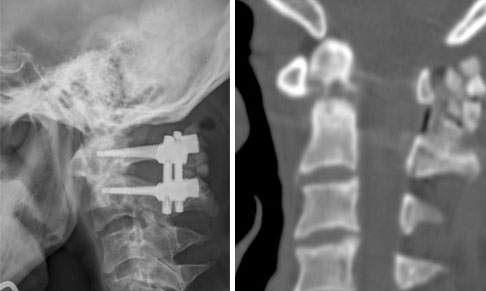

病例2  颈2齿状突骨折前路空心螺钉内固定术。

患者13岁,男性,颈2齿状突骨折。

患者受伤后2天入院,入院时四肢肌力2-3级

术后第3天

术后3个月,骨折愈合,患者四肢肌力恢复正常。